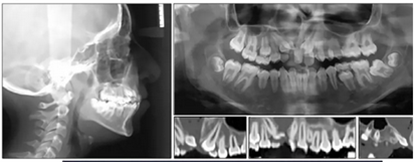

全景片示:側(cè)切牙扭轉(zhuǎn)、發(fā)育異常,影響上頜左側(cè)尖牙,下頜左側(cè)第二磨牙嚴(yán)重近中傾斜。幾乎所有的牙齒都是短根,但沒有觀察到牙根吸收的現(xiàn)象。

頭部側(cè)位片測量顯示骨性I類錯合畸形(ANB,3.5°),垂直生長模式(SN / GoMe,39°),上頜中切牙后傾(1 / SN,94°)和下頜中切牙前傾(IMPA,100 °)(圖3)。